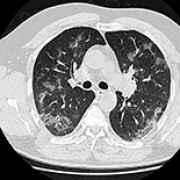

14 Nov 2021 : Clinical Research

Clinical Features and Temporal Lung Radiographic Changes in 25 Patients Recovering from COVID-19 Pneumonia: A Retrospective Case-Control Study

Chao Hu, Jian Ping Zeng, Ke Peng, Hong Xia, Huan Ming Zhang, Zhi Zhong, Ming Yan Jiang

DOI: 10.12659/MSM.933381

Med Sci Monit 2021; 27:e933381

3,640 973 0

3640 973 0